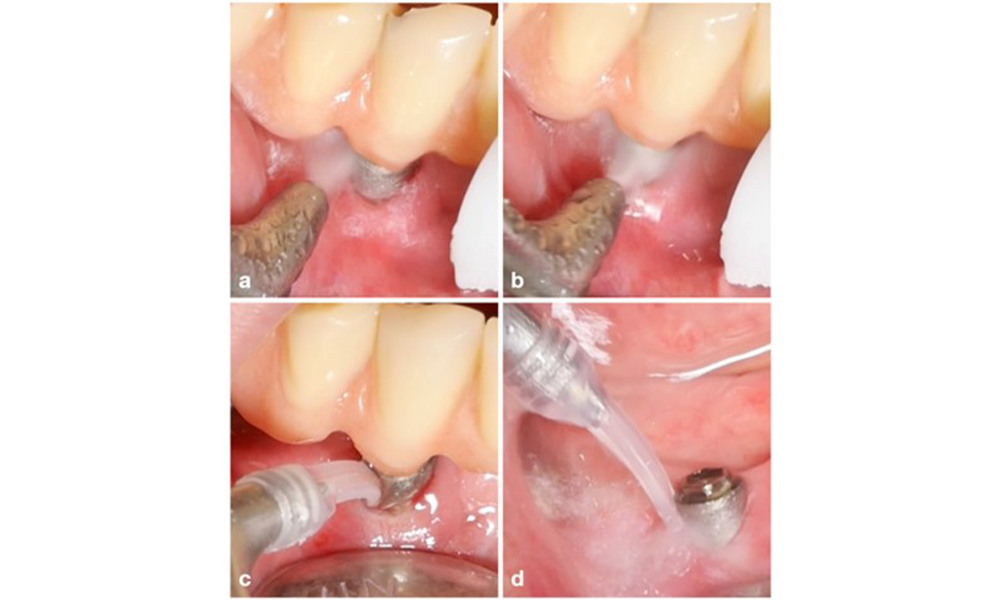

The World Workshop on the Classification of Periodontal and Peri‐Implant Diseases and Conditions from 2017 established diagnostic criteria for peri-implant mucositis and peri-implantitis (Renvert et al. 2018). Peri-implant mucositis is defined as (1) presence of inflammation around the implant (i.e., redness, swelling, line or drop of bleeding within 30 seconds of probing), combined with (2) no additional bone loss after initial healing (figure 1).

Implant in position 26 with peri-implant mucositis (a–c). The probing depth value of 5 mm (b) remains consistent with the measurement taken a few weeks after placing the prosthetic reconstruction. There is bleeding on probing (c) but the radiograph indicates no additional bone loss beyond what is expected for marginal bone remodelling (d).

Figure 1. Implant in position 26 with peri-implant mucositis (a–c). The probing depth value of 5 mm (b) remains consistent with the measurement taken a few weeks after placing the prosthetic reconstruction. There is bleeding on probing (c) but the radiograph indicates no additional bone loss beyond what is expected for marginal bone remodelling (d).

Peri-implantitis is identified by (1) signs of inflammation similar to mucositis, (2) radiographic evidence of bone loss after initial healing and (3) an increase in probing depth compared to measurements taken shortly after placing the prosthetic reconstruction (figure 2). In the absence of previous radiographs, radiographic bone level of ≥ 3 mm along with bleeding on probing and probing depths ≥ 6 mm, indicates peri‐implantitis.